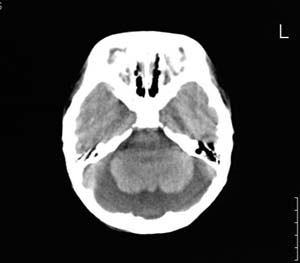

以下是引用wxy7406在2006-12-5 21:02:00的发言:[br]后颅窝囊性低密度灶,双侧小脑半球缩小,蚓部几乎缺失,考虑dandy-walker畸形,建议mri明确。

以下是引用阿圣在2006-12-5 20:55:00的发言:[br]后颅窝囊性低密度灶,双侧小脑半球缩小,蚓部几乎缺失,考虑dandy-walker畸形,建议mri明确